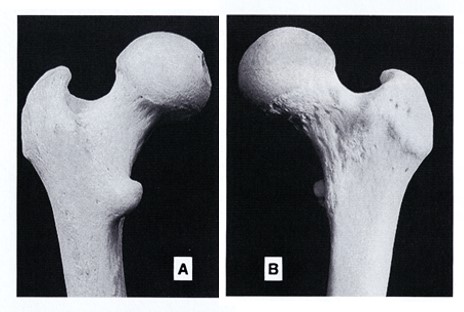

【大腿骨近位部骨密度測定】

・大腿骨骨幹部軸と体軸が平行になるように測定する。

・股関節内旋・外旋は、骨密度に大きな影響を与える。小転子が小さく見えるのが適切な回旋である(図5)。小転子が大きく見えるのは外旋が強く、全く見えないのは内旋が強い。

ClinicalTips03_06.jpg

図5. 大腿骨近位部

(A) 背側から見た大腿骨近位部

(B) 腹側から見た大腿骨近位部

頸部が最も正面にあり、広く見えるとき、小転子は小さく見える

(出典:McMinn RMH, Hutchings RT, Pegington J, and Abrahams PH. 1993 Color atlas of human anatomy, 3rd ed by permission of Mosby International.)